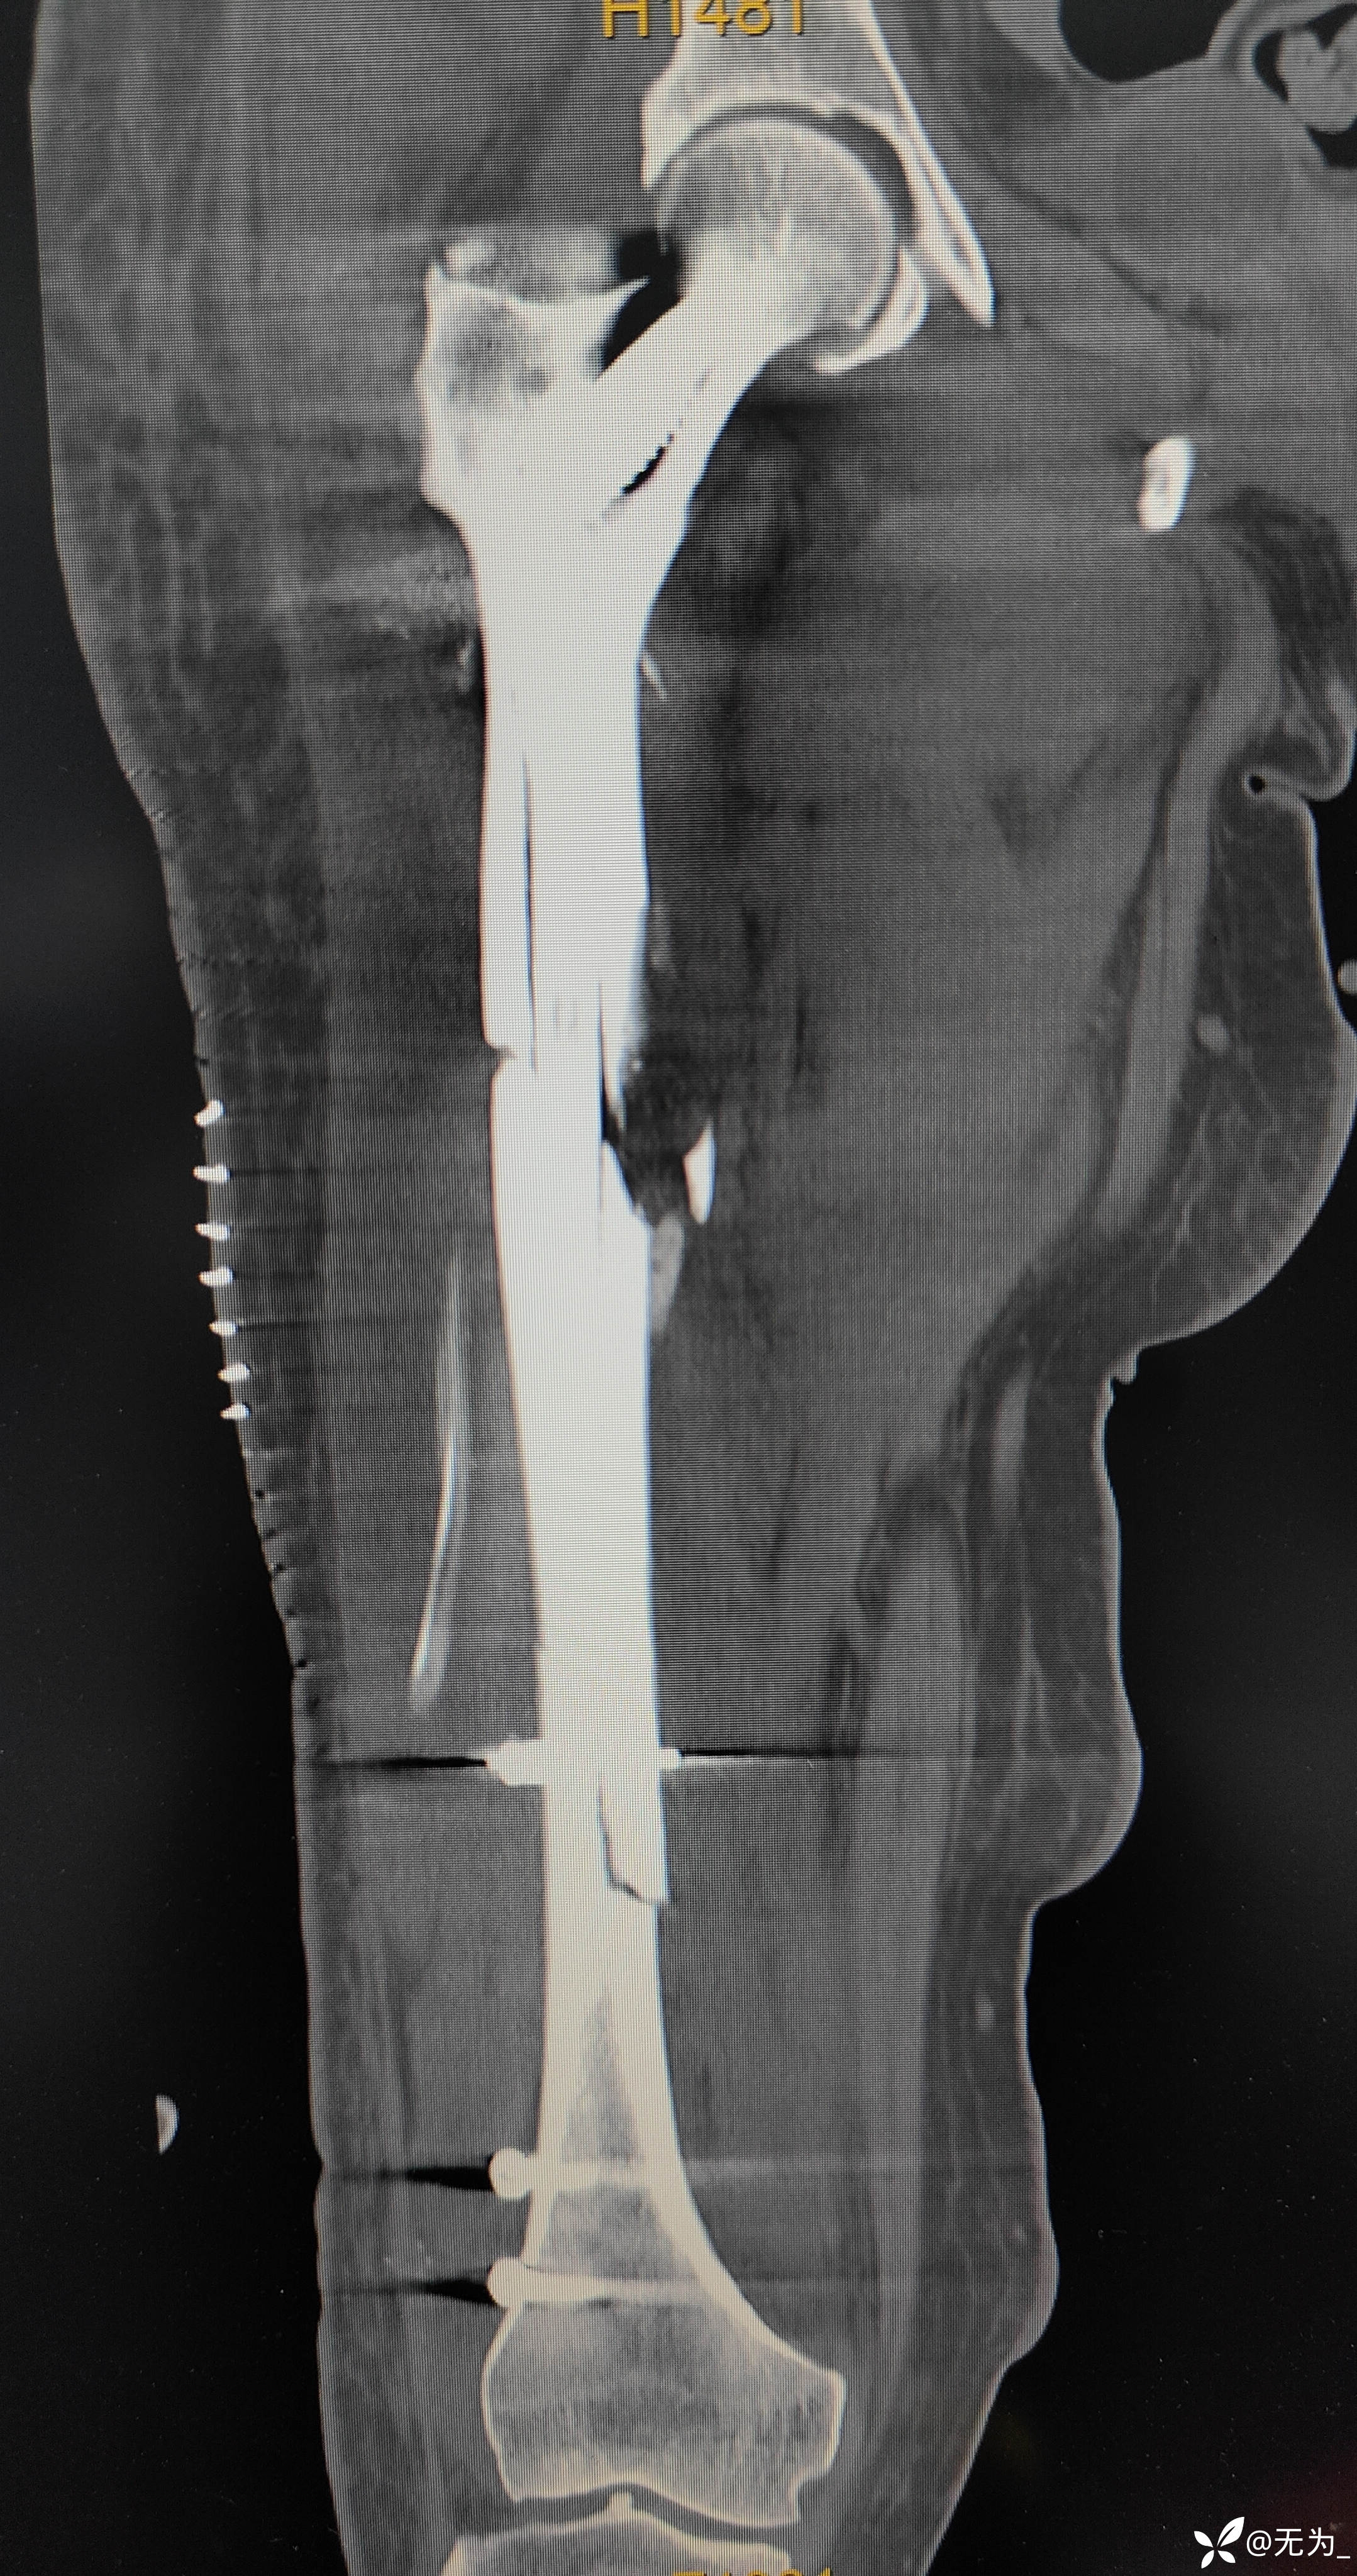

查体:右大腿中段前外侧两公分开放伤口,渗血,可处理游离骨块,大腿畸形、肿胀,足背动脉搏动可查。

补液、输血后行头外伤缝合、大腿外架临时固定,转icu,病情逐渐稳定,3周后行右股骨外架拆除,复位内固定。

三段骨折,复位困难且时间长,患者取侧卧位,取大腿外侧切口,切开以后大量肉芽组织,清理折断,牵引复位,远折断钛揽固定,近折端钳夹复位,开孔、扩髓,置入髓内钉,螺钉固定,内侧骨块未处理伴骨缺损,未植骨避免感染。